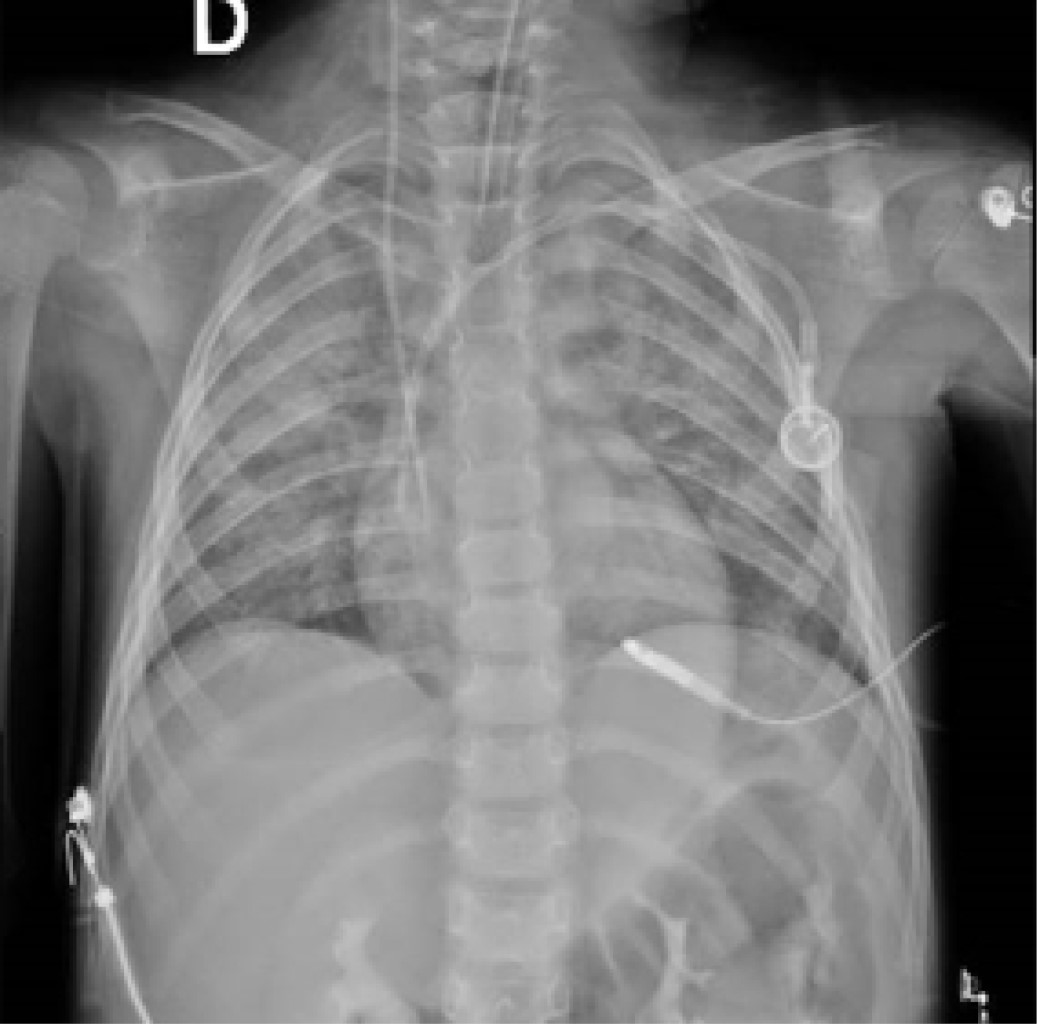

Pneumonia in an immunocompromised pediatric patient

Figure 1